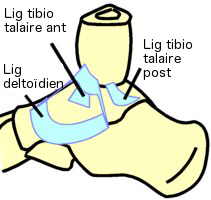

Le ligament collatéral médial est

disposé en 2 plans

- Plan superficiel (ligament deltoïdien, non dessiné

dans sa totalité) s'étend en éventail du bord

antérieur de la malléole médiale à la face interne du

naviculaire jusqu'au calcanéus

- Plan profond avec un faisceau antérieur (ligament tibio

talaire ant.) s'étend du bord antérieur de la malléole

médiale au collier du talus, et un faisceau postérieur

(ligament tibio talaire post.) symétrique au

précédent, qui se termine sur la face postérieure du

talus.

|

Vue

médiale pied D

|